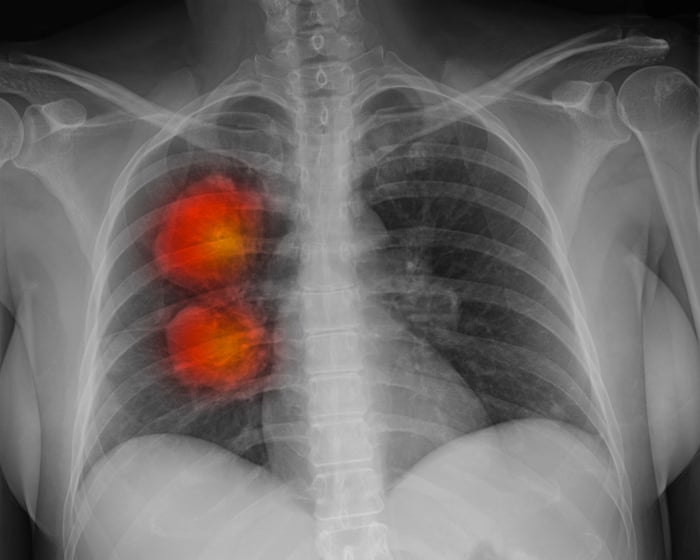

A recent analysis by Radiotherapy UK reveals a troubling situation for cancer patients in England, with over 60,000 not receiving the necessary radiotherapy each year. The report highlights that some patients are facing waits of up to six months to start their treatment. This alarming trend has prompted nearly 100 leaders in radiotherapy and oncology to issue an open letter expressing their concerns. The implications of these delays are significant, as timely access to treatment is crucial for improving patient outcomes and survival rates.